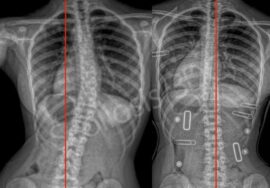

إذا لاحظتِ علامات انحناء في ظهر طفلك، أو لاحظتِ عدم تماثل بين الجانبين، فلا تتردد الأن في استشارة مجانيه من طبيب متخصص.